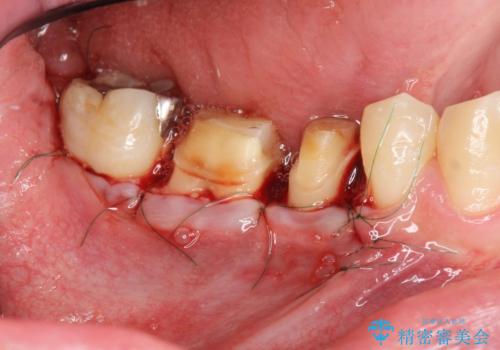

深い虫歯 セラミッククラウンの精度を高める歯周外科手術

- 歯ぐきからの排膿や出血、根尖病変の存在により他院で抜歯を提案され、歯を残す方はないかと当院に相談に見えました。

マイクロスコープを用いた根管治療を行ったのち、深い虫歯に起因する歯ぐきの腫れ・出血を改善すべく歯周外科を行いました。